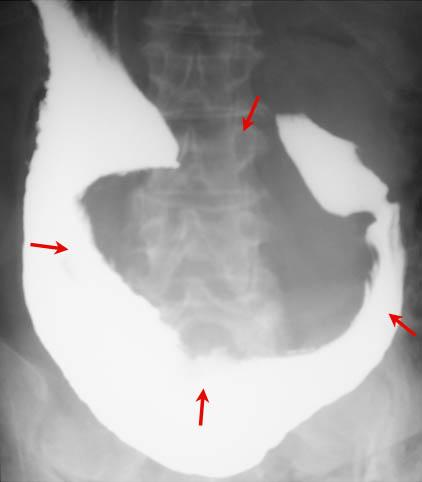

症例提示(所在地,施設名等): 佐賀県・ 唐津赤十字病院 (放射線科、永尾英毅先生からの提供症例)

疾患(病理主体)の分類悪性非上皮性腫瘍/平滑筋肉腫(含GIST)

部位(臓器別)胃(部位)/2つ以上

検査方法X-P

病変の最大径(ミリ)40以上